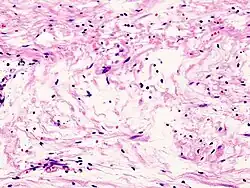

Guz zbudowany jest z jednorodnych komórek o morfologii komórek Schwanna. Jądra komórkowe są wydłużone, układają się w wiry, pasma lub palisady. Charakterystyczne dla guza jest tworzenie tzw. ciałek Verocaya. W części przypadków wraz ze wzrostem gęstości komórkowej jądra przyjmują okrągły lub wieloboczny kształt. Typ histologiczny w którym komórki są zbite i ustawione palisadowato określa się jako Antoni A; typ w którym komórki są ułożone nieregularnie i luźno to typ Antoni B.